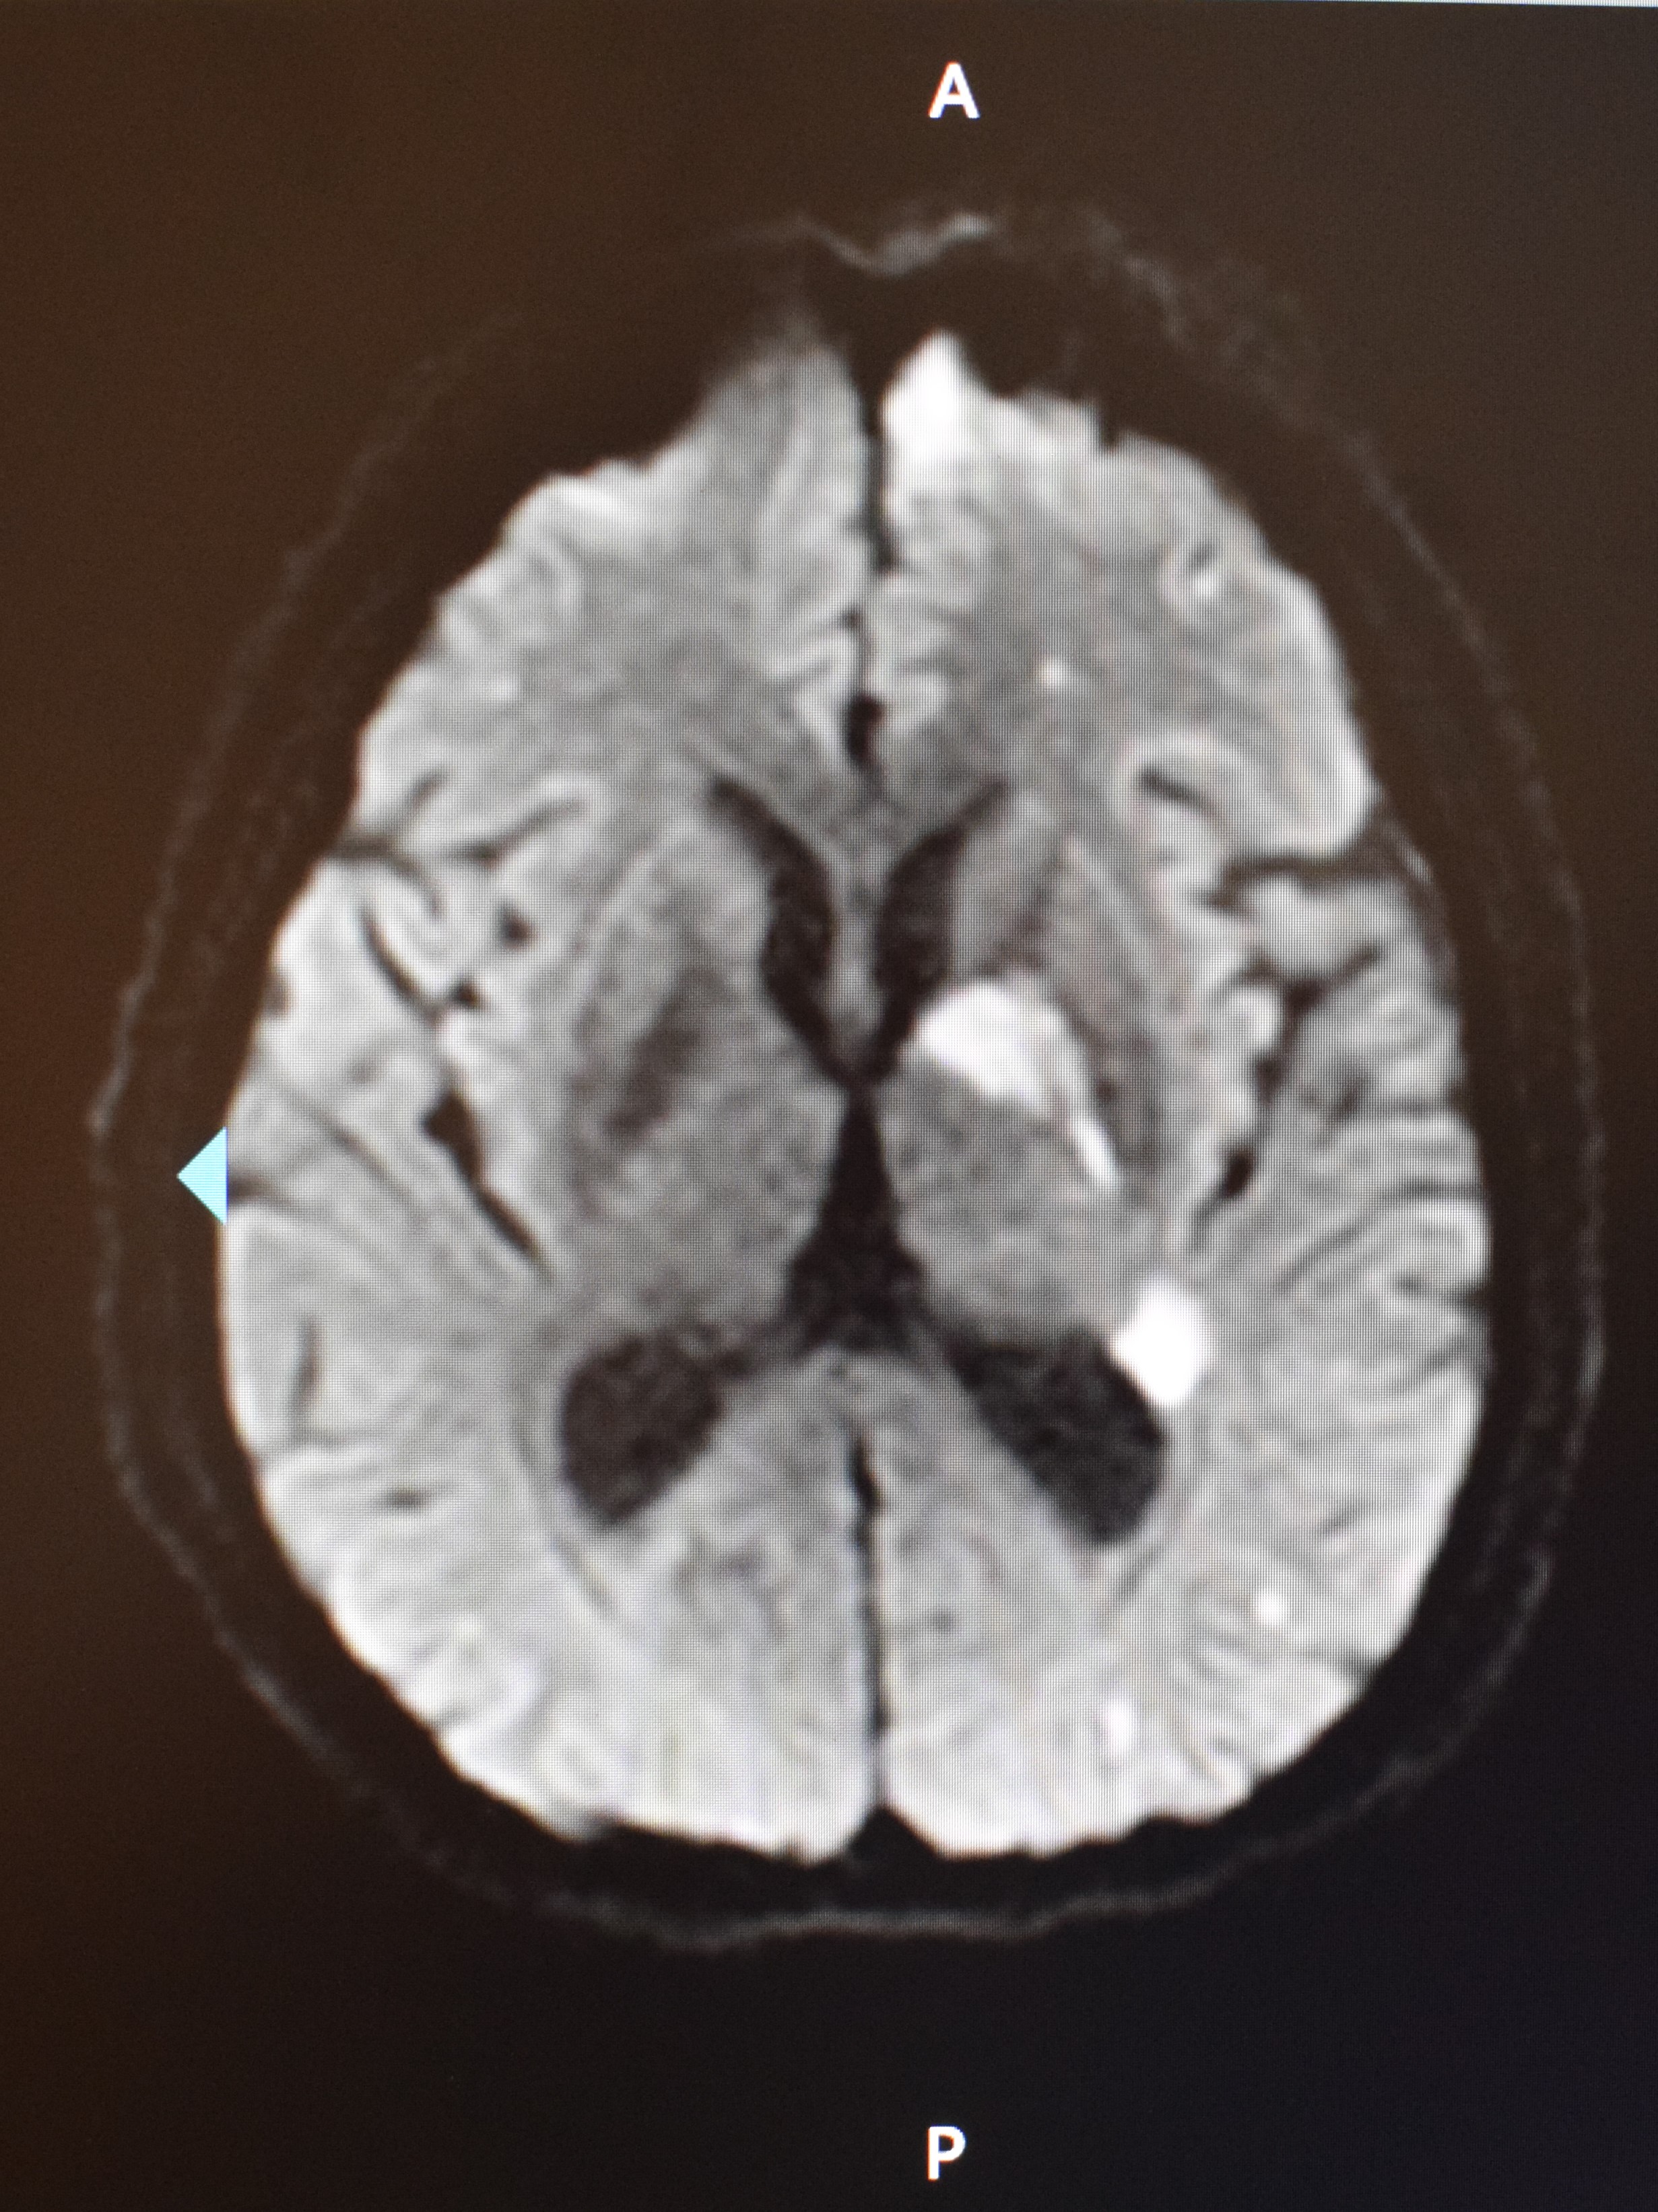

8月25日行鼻内镜下左侧鼻腔、鼻窦、颅底感染清创术与左侧眶内侧壁、眶底壁减压术。术中见左侧鼻腔外侧壁、下鼻甲、鼻顶、鼻中隔黏膜大面积坏死、结痂,左侧鼻泪管、眶筋膜以及面部软组织受累,眶内脂肪组织水肿。术中冷冻快速病理:送检组织慢性炎,另见炎性坏死组织,其内查见真菌菌团,考虑毛霉菌感染(见图 3)。术后第1天发热,体温最高38.0 ℃,给予口服泊沙康唑、头孢曲松,胰岛素控制血糖等治疗。G试验和GM试验阴性,鼻拭子细菌培养阴性。患者于8月28日20:00出现言语混乱、右侧肢体肌力降低,MRI示左侧大脑半球、基底节区多发急性梗死(见图 4),皮下注射依诺肝素钠注射液40 mg每12 h一次抗凝、口服阿司匹林100 mg 3次/d抗血小板、扩血管等治疗。患者眶蜂窝织炎,请眼科会诊,建议继续抗感染治疗、处理脑梗死,待病情平稳后处理眼部病变。经过抗感染治疗,患者仍反复发热,结合患者嗜睡等,考虑可能合并颅内感染,将抗生素升级为美罗培南。于8月30日回当地医院继续治疗。

|

| 患者颅脑MRI(DWI)示左侧大脑半球、基底节区多发急性梗死 图 4 患者8月28日颅脑MRI(DWI) |